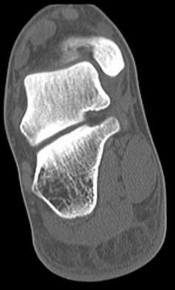

QUESTION 4

Figures 4a through 4j

1

Normal foot

- Normal foot

Figures 4a through 4j do not show any signs of a coalition.